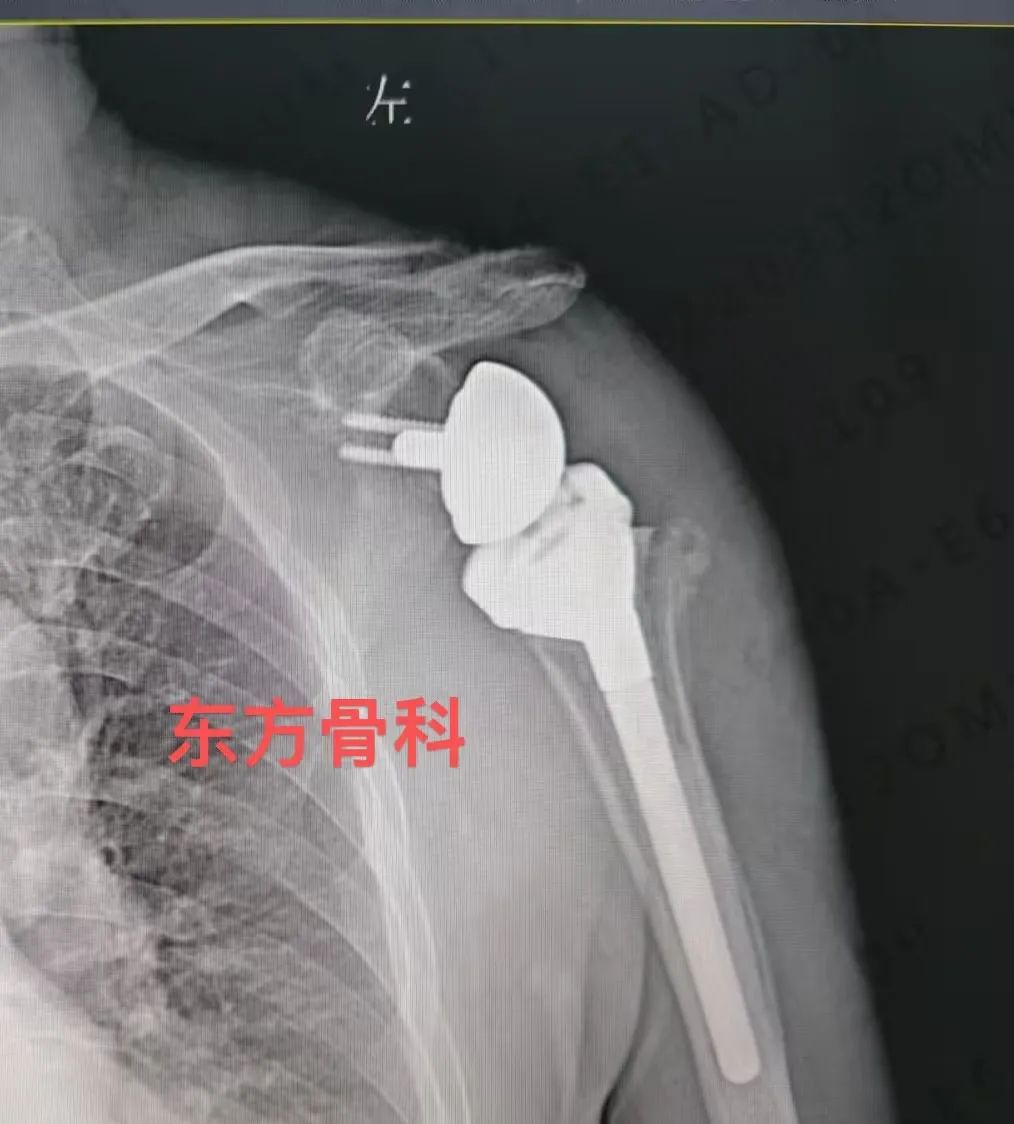

淮南东方医院集团骨科医疗中心江涛院长带领团队,经过仔细的术前检查和讨论,为郑大爷制定了周密的手术规划,考虑到患者高龄,为尽快解除痛苦,恢复运动功能,详细评估患者情况后,准备对患者 拟行“反式人工肩关节置换术”,在征得家属同意后,江院长带领团队对患者进行手术,过程顺利,患者积极康复中。

江院长介绍:反式全肩关节置换术( RTSA)是一种对手术技术及配合要求极高的手术。此手术是指肩关节假体的球形关节面放置于肩胛骨关节盂侧,而盂杯放置于肱骨近端的半限制性人工全肩关节,与正常的肱盂关节配对形式正好相反。该术式可以更好地发挥三角肌动力性作用,完成肩关节外展、前屈及内旋活动,从而降低肩关节对肩袖完整性的依赖。另外,该手术需要时间短、并发症少,可有效消除疼痛,快速恢复患者关节功能,提高生活质量。